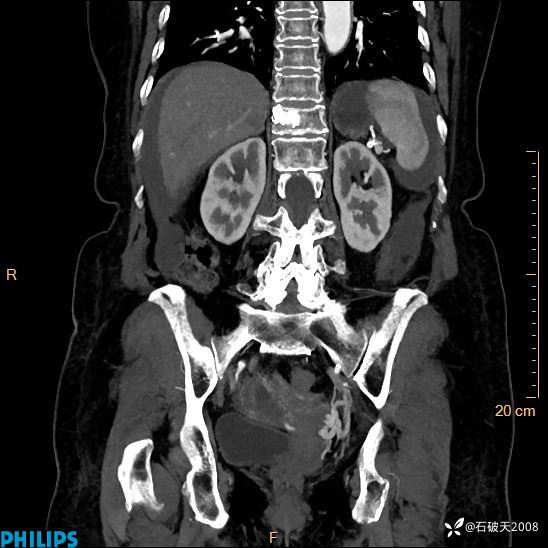

动脉期